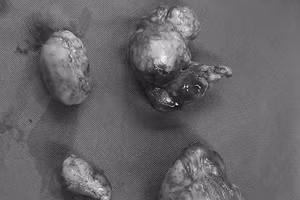

GD&TĐ - Bệnh viện Việt Nam - Thụy Điển Uông Bí (Quảng Ninh) vừa tiến hành phẫu thuật lấy thai lần 3 cùng với bóc tách, cắt bỏ 4 khối u xơ, bảo tồn tử cung cho sản phụ.

GD&TĐ - Luật gia cho rằng, cơ quan chức năng sẽ làm rõ ai là người vứt thai nhi ra vị trí này để có hình thức xử lý và thực hiện các giải pháp phòng ngừa theo quy định pháp luật.